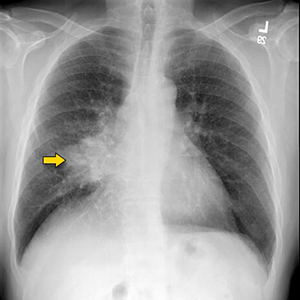

Yes. Your doctor after examining you may advice Chest X-ray. If the chest X-ray is suspicious of lung cancer, he or she will probably follow up with other tests. These can include: